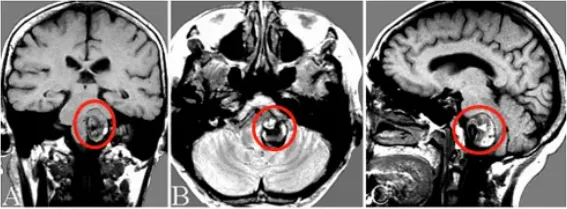

20岁的小峰正值青春年少,努力奔跑、勇敢追梦的年纪,刚上大学的他人生刚刚开始。 然而命运不幸遭遇无情的脑干血管畸形,一次高达4ml的脑干出血,引起了肥大性下橄榄核变性(...